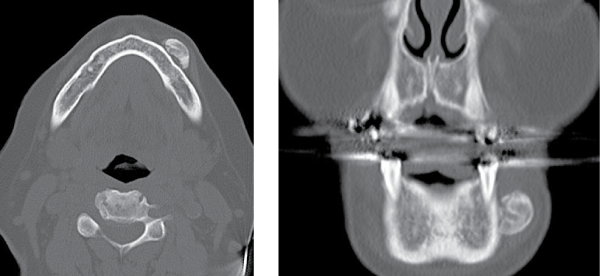

Two years later the patient returned with a new mass in the same area of previous excision. An excisional biopsy was performed. This specimen was fixed in formalin and sent for histopathological examination. The gross appearance of the recurrent mass was that of a single piece of white-pink solid tissue, with dimensions of 0.9 × 0.8 × 0.6 cm. Histological sections contained mature lamellar bone with focal superimposed areas of woven bone, arranged mainly in trabeculae with peripheral areas of thicker, cortical bone (Figure 2). Some fatty marrow was present; however, there was no hematopoiesis. The bone in the sections appeared to have an increased number of osteocytes (in comparison to normal lamellar bone), but there was no appreciable atypia or mitotic activity (Figure 2). The bone was one large fragment with several submillimeter satellite nodules located in the surrounding fibrous tissue.

Figure 2: A - Low power photomicrograph of recurrence, showing mature bone forming vague lobules and surrounded by a rim of fibrous tissue (artifactually separated). Note fatty marrow (right) and small satellite foci of bone (far left). (H&E, 20x). B - Higher power image of recurrence, showing mature lamellar bone lacking any atypia of the individual osteocytes (H&E 200x)